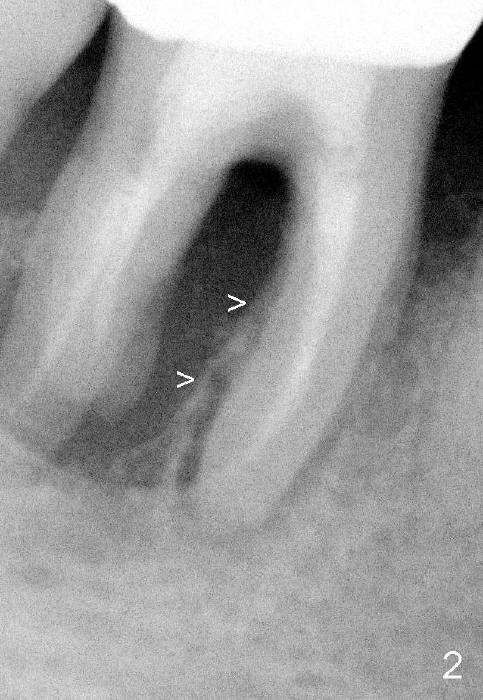

Fig.1,2 show bone resorption of the distobuccal and distolingual roots of the lower right 1st molar. The septum is present preop (Fig.2 >).

Fig.3 shows a 4.5x17 mm tap in the mesial socket (not stable). There is 7.14 mm bone between the end of the tap and the upper border of the inferior alveolar canal (red dashed line). The coronal end of the septal bone (Fig.4 >) is as high as the mesial crest.